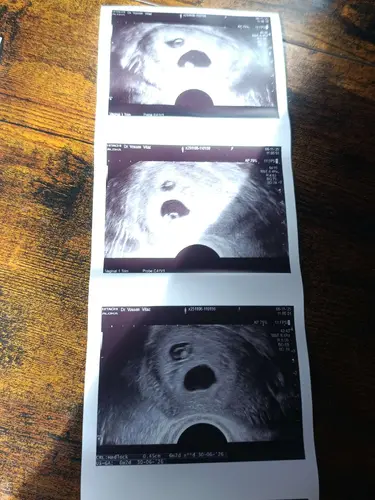

Bij ons was er een vermoeden van minstens een week verschil in bevruchting, zelfs twee weken. Je kon dit duidelijk zien op de eerste echo's dat ze in andere fase van ontwikkeling waren, niet enkel een kleinere variant.

Hoeveel verschil zat er tussen? Bij ons is al vanaf het begin een verschil van meer als een week, ze groeien wel mooi parallel. Maar bij 1 was er op 6w4d nog geen hartactiviteit.. en toen de andere een week ervoor 6w5d was er bij dat kindje wel al hartactiviteit (dat was wel een veel nieuwer echo toestel.. bij het kleinste was het bij de gynaecoloog met een heel oud waar je zelfs geen scherp beeld hebt). Ik ben wanhopig op zoek naar succes verhalen.. ik weet zelf pas de 26e meer.